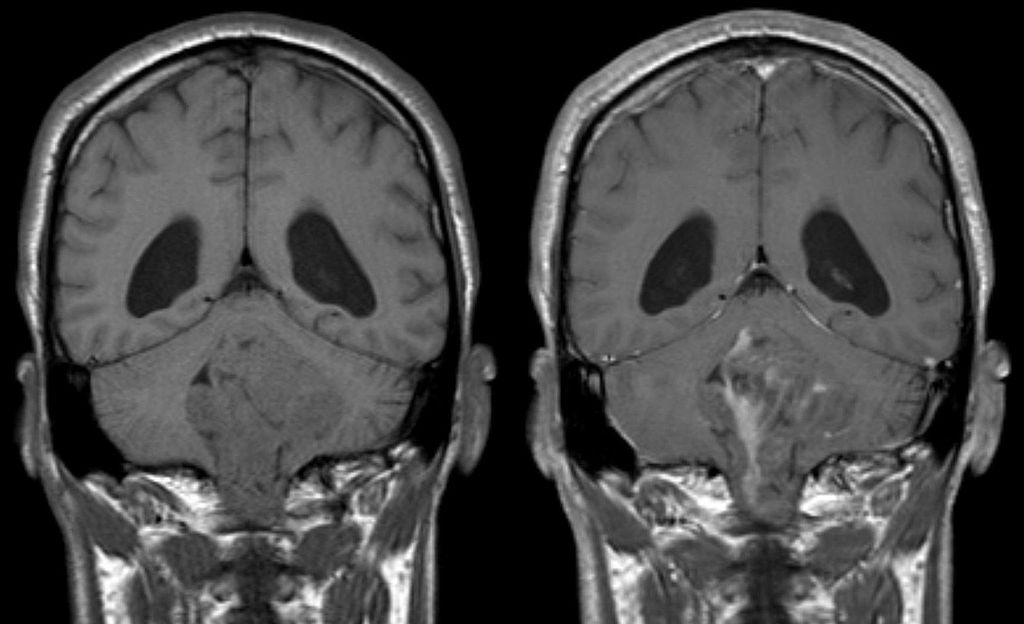

Η πρωτοβουλία ανήκει στο Υπουργείο Υγείας της Καλιφόρνια, οι επιστήμονες του οποίου δήλωσαν, ότι «πρόθεσή τους είναι να βοηθήσουν τους ανθρώπους που ανησυχούν για τους κινδύνους που μπορεί να αντιμετωπίζουν με την υγεία τους, συμπεριλαμβανομένων των όγκων στον εγκέφαλο, τη μείωση του αριθμού των σπερματοζωαρίων, τα προβλήματα στη μνήμη, τη μάθηση και τον ύπνο».

Μία μελέτη που εξέτασε πάνω από 5.000 περιπτώσεις καρκίνου του εγκεφάλου σε 13 χώρες δεν εντόπισε αύξηση του κινδύνου που σχετίζεται με τη χρήση του τηλεφώνου, αν και αναφέρεται στα συμπεράσματα, ότι απαιτείται περισσότερη έρευνα για το θέμα.